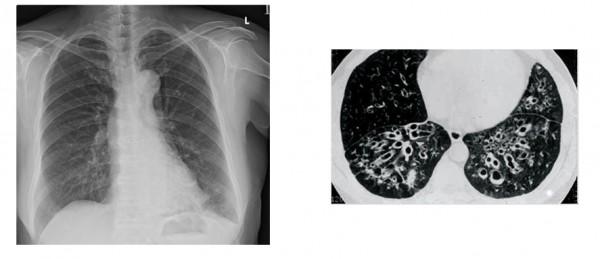

기관지 확장증, 주요 증상과 치료 방법 총정리

기관지 확장증은 기관지의 비정상적인 확장을 의미하며, 이를 경험하는 환자들은 주로 가래, 기침, 호흡 곤란 등의 증상을 겪게 됩니다. 이러한 증상들은 일상생활에 큰 영향을 미칠 수 있으며, 질병의 원인과 치료 방법에 대한 체계적인 이해가 더욱 필요합니다. 이번 포스트에서는 기관지 확장증의 주요 증상과 치료 방법을 총정리하겠습니다. 살면서 알레르기나 감기와 같은 사소한 건강 문제를 겪으면서도, 내 몸의 변화에 대한 소홀함이 후에 큰 문제가 될 수 있음을 잊지 말아야 합니다.